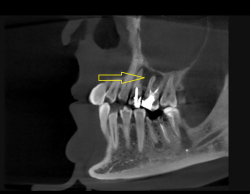

Ранее пациентка консультировалась у ЛОР-специалиста и нескольких стоматологов из других клиник- пациентке был предложен единственный вариант лечения, связанный с удалением двух проблемных зубов с воспалительным процессом на верхней челюсти , плюс проведение консервативного ЛОР лечения. Пациентка с вариантом удаления двух зубов не согласилась и обратилась к нам в клинику. После проведения диагностических мероприятий было установлено наличие обширных воспалительных процессов на двух зубах на верхней челюсти, а также на нижнем зубе.

Нами было проведено повторное эндодонтическое лечение проблемных зубов.Через 6 месяцев видны отличные результаты заживления воспалительных изменений на верхушках корней, а также устранение воспаления в верхнечелюстной пазухе( гайморита).